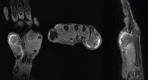

Case report: We have included five cases of osteochondromas occurring at rare locations with variable presentations and their management. We have included one case of metacarpal, one case of skull exostosis, two cases of scapula exostosis, and one case of fibula exostosis.